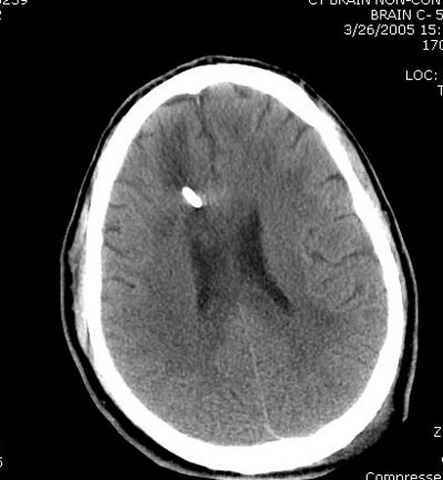

Наблюдается службой травмы и нейрохирургии (ICP) Increased Intracranial Pressure by ventricular cateter

больной без сознания, со слов нейрохирурга, наблюдается положительная динамика в нейрохирургическом статусе.

монииторинг